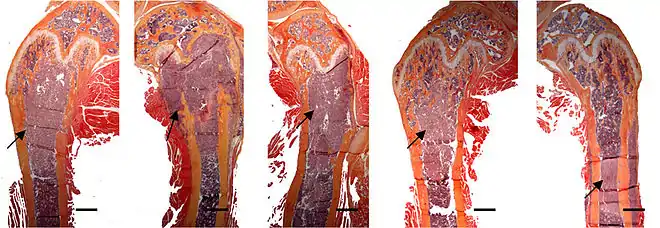

Pour la recherche des métastases osseuses, sa prévention et sa thérapeutique, on utilise avant tout l'organisme modèle la souris, en particulier la souris « nude ». Chez les souris avec ce défaut immunitaire, on peut inoculer des cellules tumorales humaines, qui se développent après quelques semaines en métastases osseuses[63].